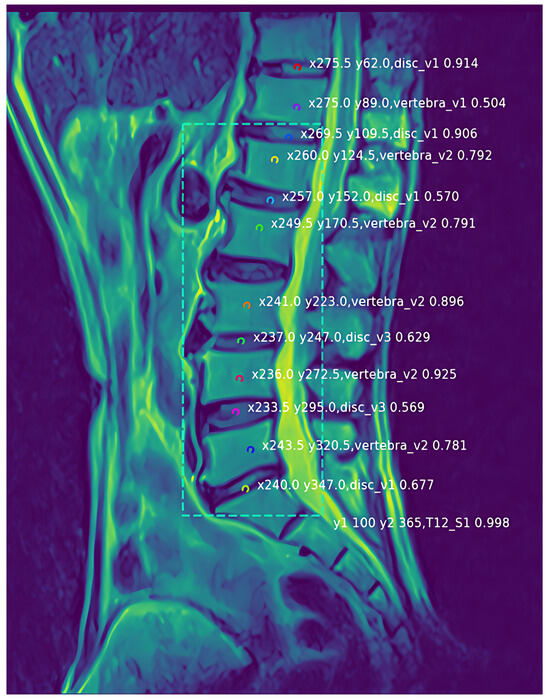

Figure 10 presents a prediction output map randomly selected in the test set. The prediction outputs the position coordinates x and y of the prediction point and also outputs the class of each prediction point and the probability p of the class. Through observation, it can be found that the positioning points in the figure are relatively accurate, the prediction points are basically in the middle area of the vertebra and the disc. The positioning task is highly completed. However, because there are still intervertebral discs and vertebral bodies that are not part of the lumbar spine, and their characteristics are similar. Therefore, it can be found that a small number of discs and vertebrae other than T12_S1 are also located and predicted, so the added T12_S1 category can be used to exclude non-lumbar discs and vertebral bodies, making the positioning more accurate.